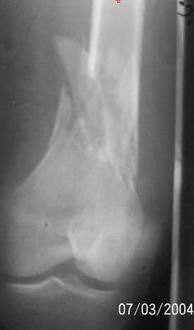

A 34 year old male was injured in a car accident.

The femur injury was treated by long retrograde interlocking nail.

Need an Opinion on this Case.